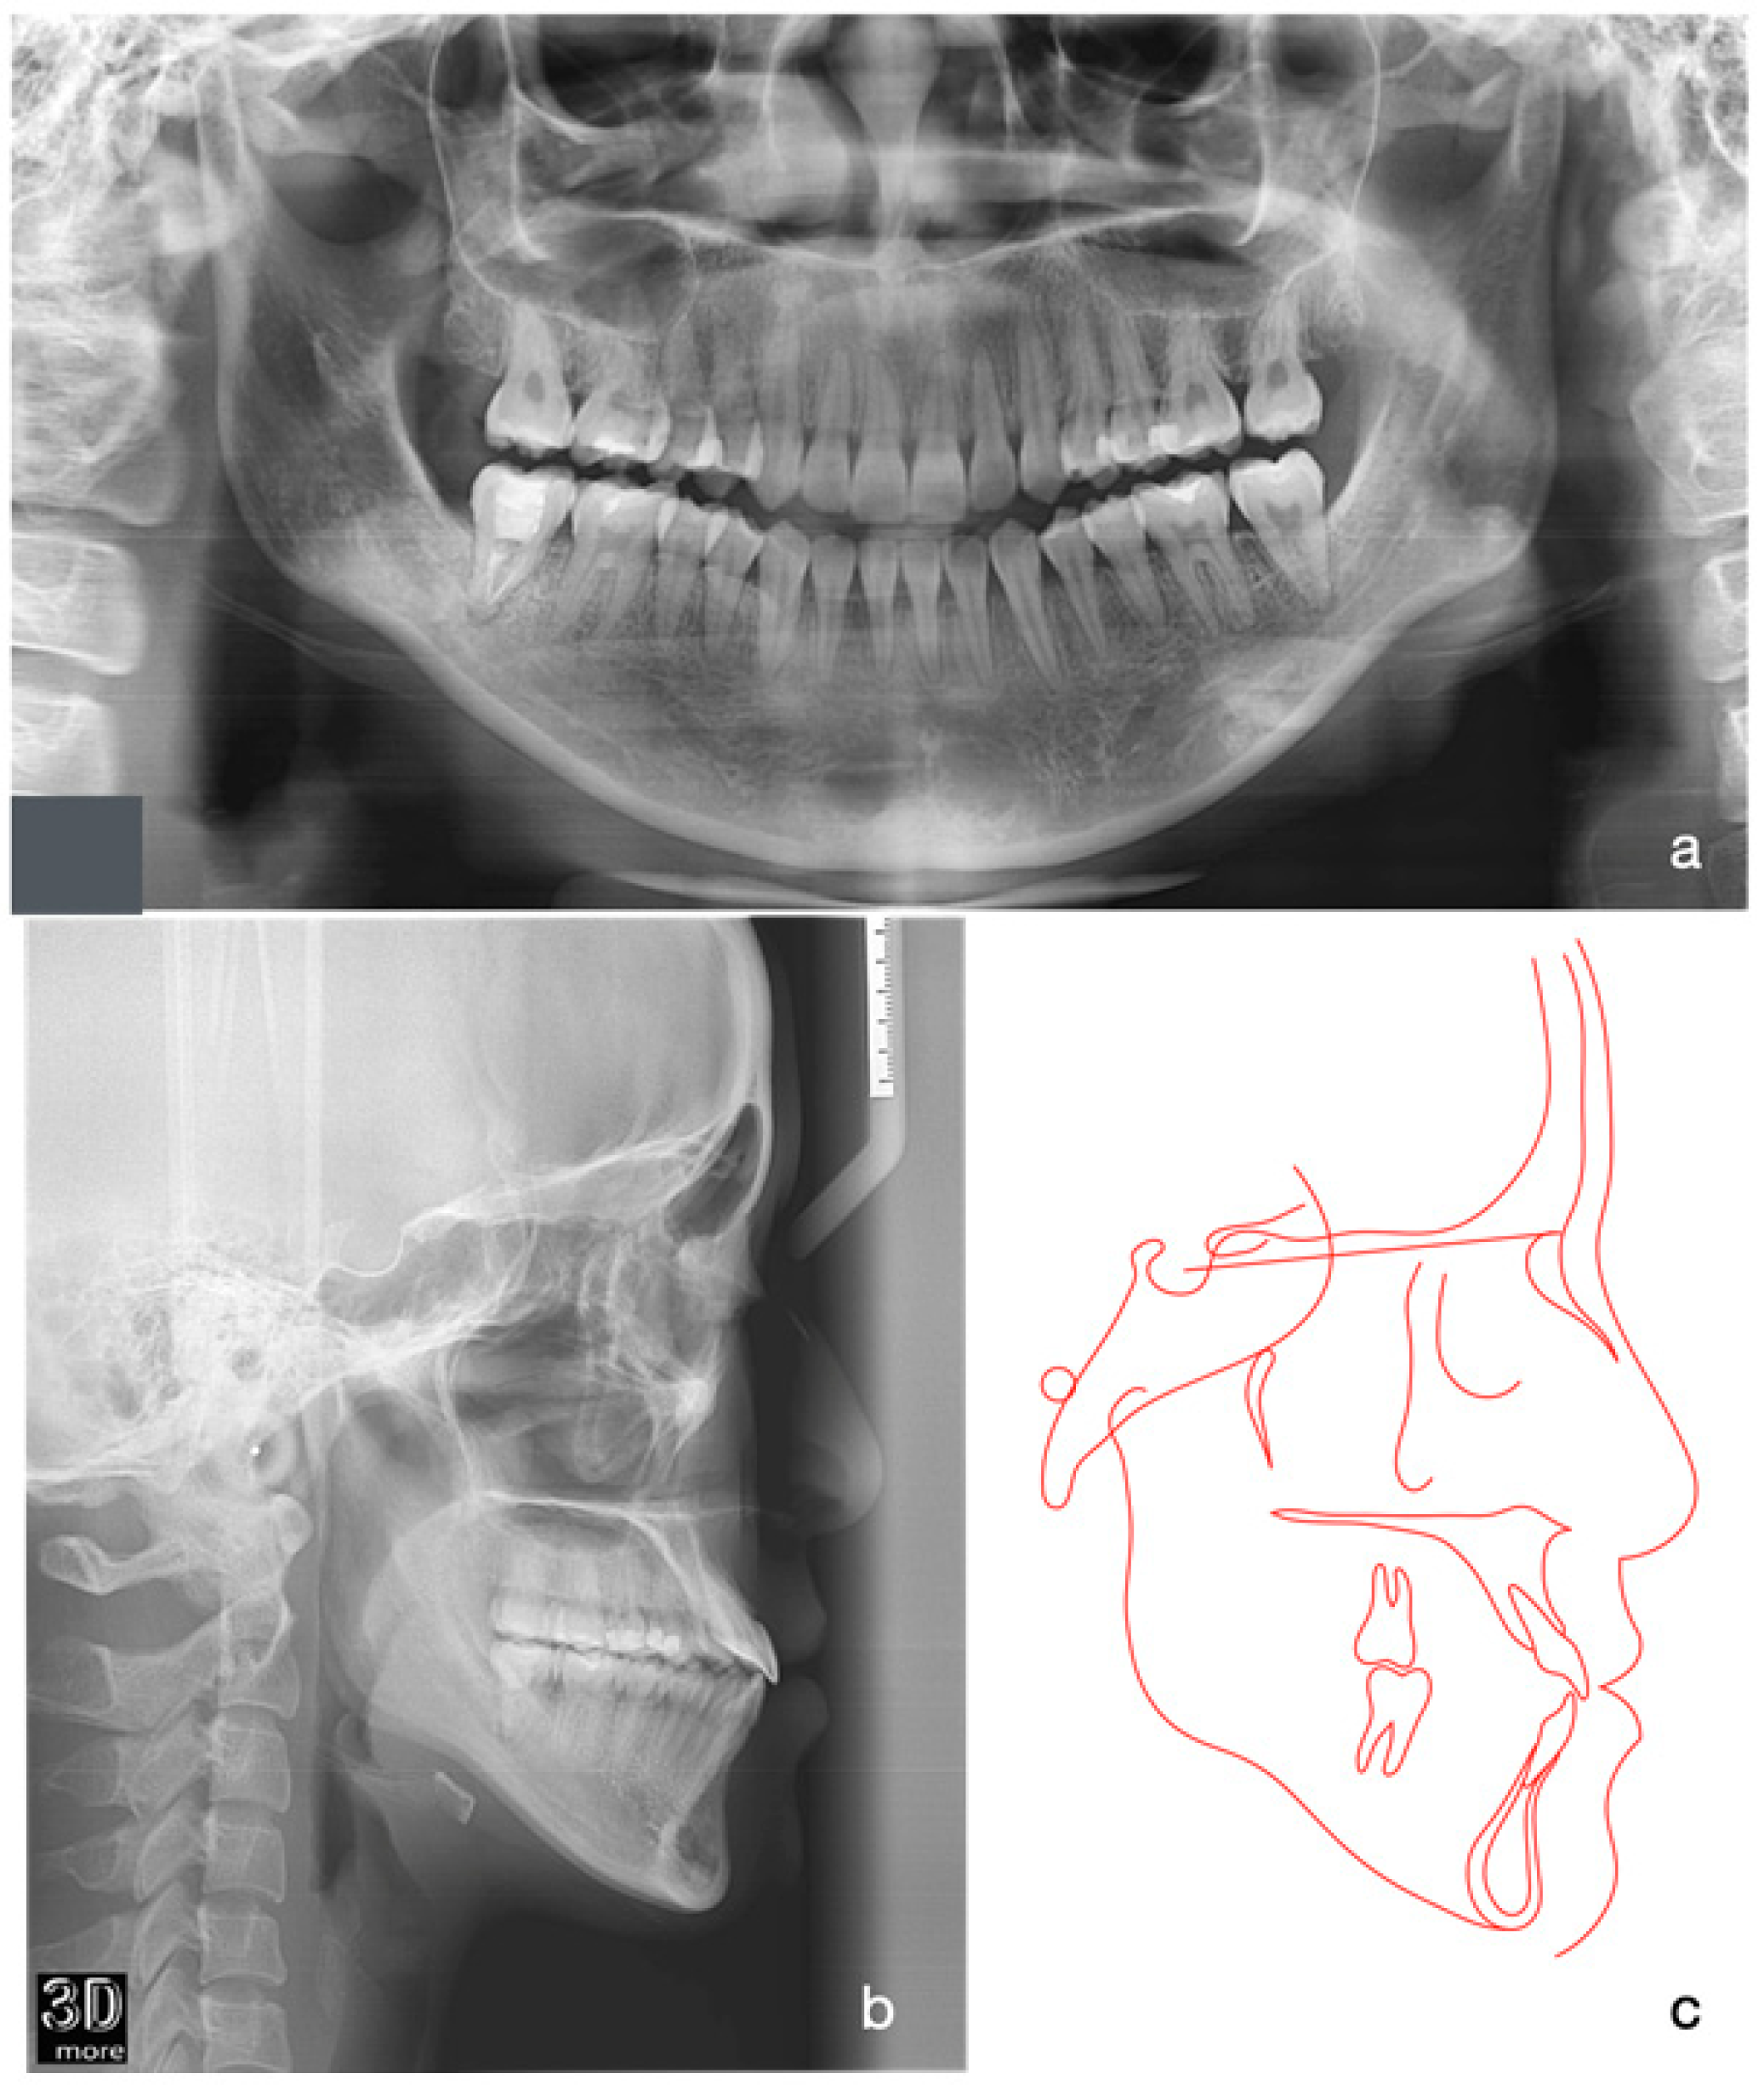

2.4. Treatment Progress

2.5. Treatment Results